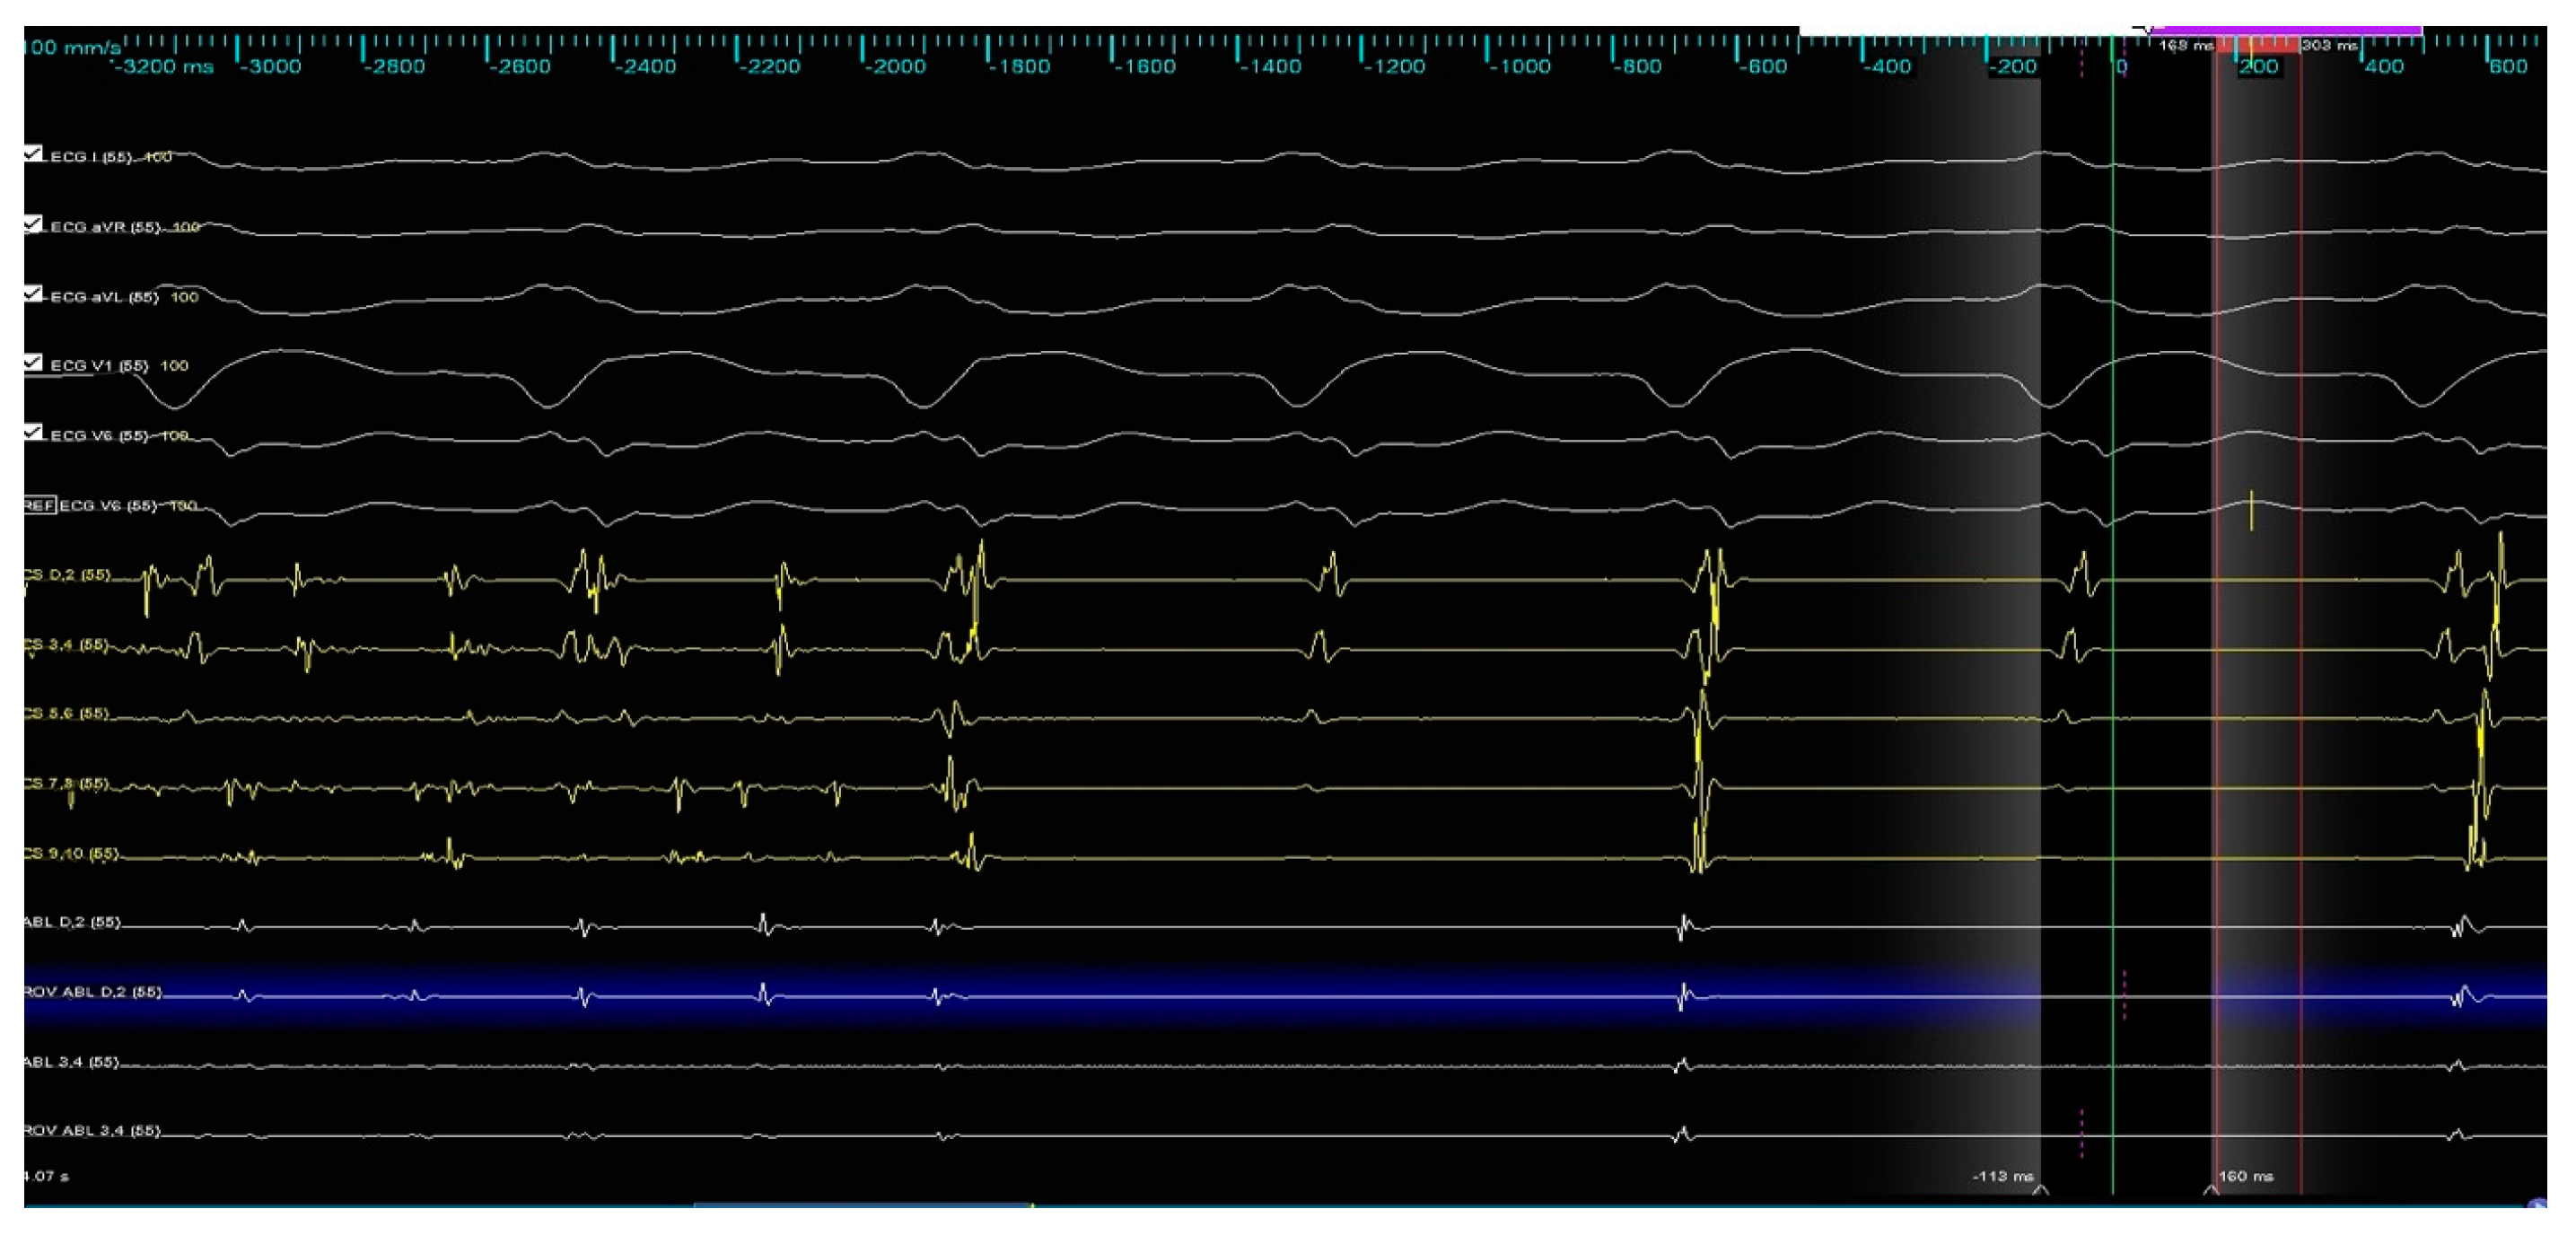

During the ablation of the infero-posterior aspect of the right inferior pulmonary vein, spontaneous restoration of sinus rhythm occurred and was maintained until the end of the procedure (Figure 7).

Figure 7. Termination of atrial fibrillation during RF application.